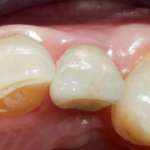

Restauri diretti in composito bulk-fill a viscosità variabile Premium

Viene presentato un caso clinico con lo scopo di comprovare l’efficacia della tecnica bulk-fill diretta a viscosità variabile, come alternativa a un restauro con tecnica a strati, senza comprometterne estetica e funzionalità.